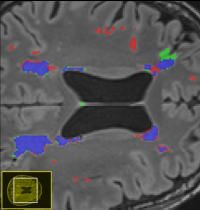

• Interdisciplinary Bachelor thesis in the domain of "Automated Segmentation of WMH"

BA WMH Segmentation

White matter hyperintensities (WMHs) are among the signs of vascular dementia on conventional MRI. In this thesis, relevant automated algorithms for segmentation of WMHs shall be compared for their performance on a clinical cohort.